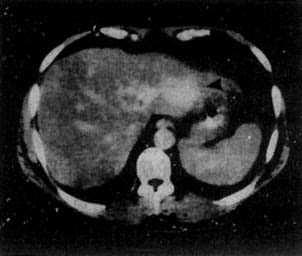

原发性肝癌

图4-3-5 原发性肝癌

CT增强扫描,肝右叶有一较大圆形低密度肿块(↓),其边缘

部可见多个较密度的强化结节,其强化程度不如正常肝,中

心部仍为未强化的低密度区